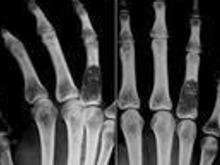

3.X線拍片顯示:患指骨質有破壞等。